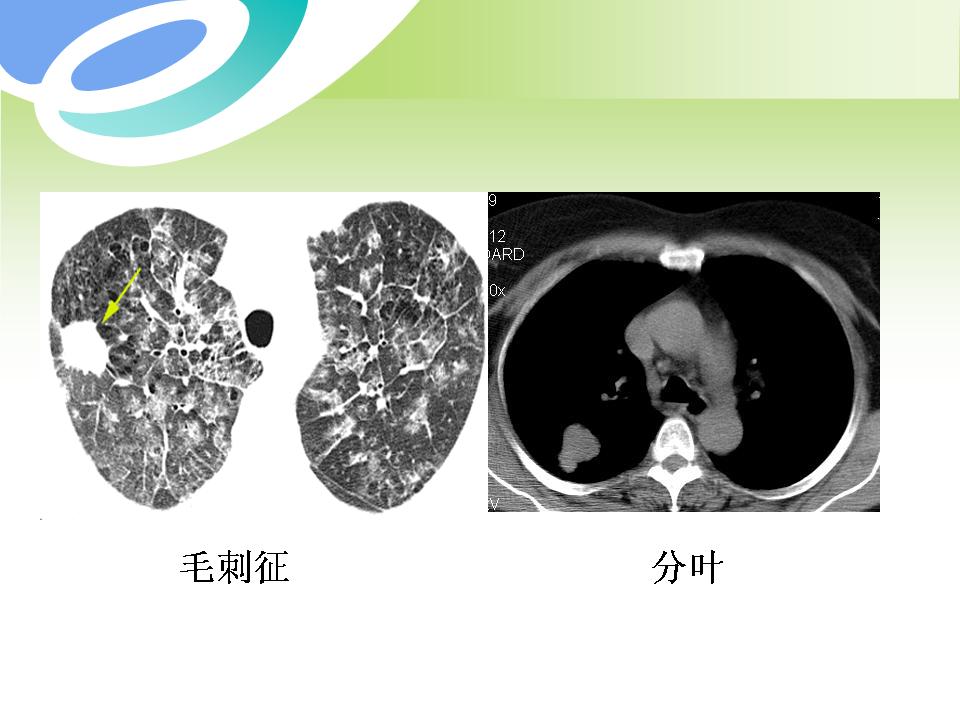

肺部病变的CT基本征象